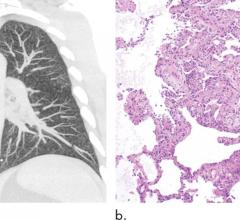

November 23, 2021 — Median Technologies announces new outstanding performance of its lung cancer screening (LCS) CADx1 ...